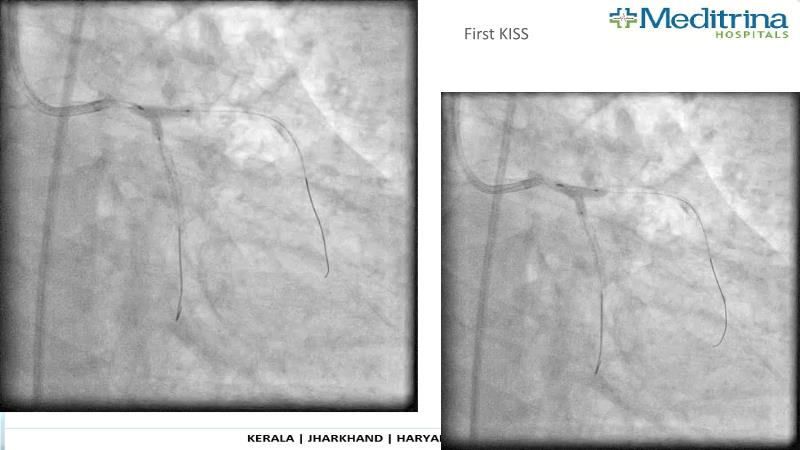

- To define the use of OCT in PCI of complex coronary lesions